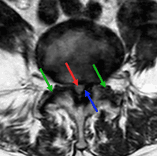

Souffrance radiculaire de la racine de C7 par une hernie discale

MRI